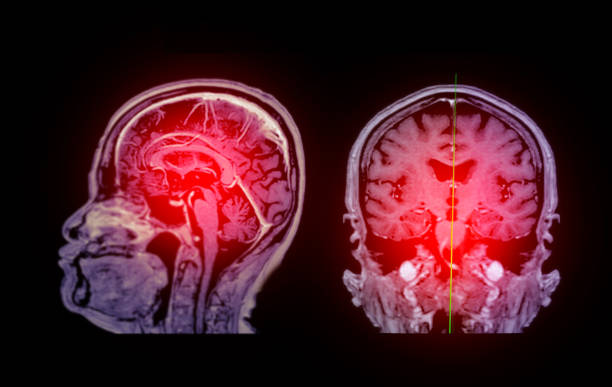

缺血性腦卒中,又稱腦梗死,是一種因腦部血液循環(huán)障礙導(dǎo)致的腦組織壞死疾病。它給患者帶來的不僅是身體上的痛苦,更是心理上的巨大壓力。

據(jù)統(tǒng)計(jì),我國已成為腦梗的重災(zāi)區(qū),每年新增的腦梗患者500多萬,而現(xiàn)有的治療方法往往難以完全恢復(fù)受損的神經(jīng)功能。因此,尋找新的、更有效的治療方法一直是醫(yī)學(xué)界的研究重點(diǎn)。